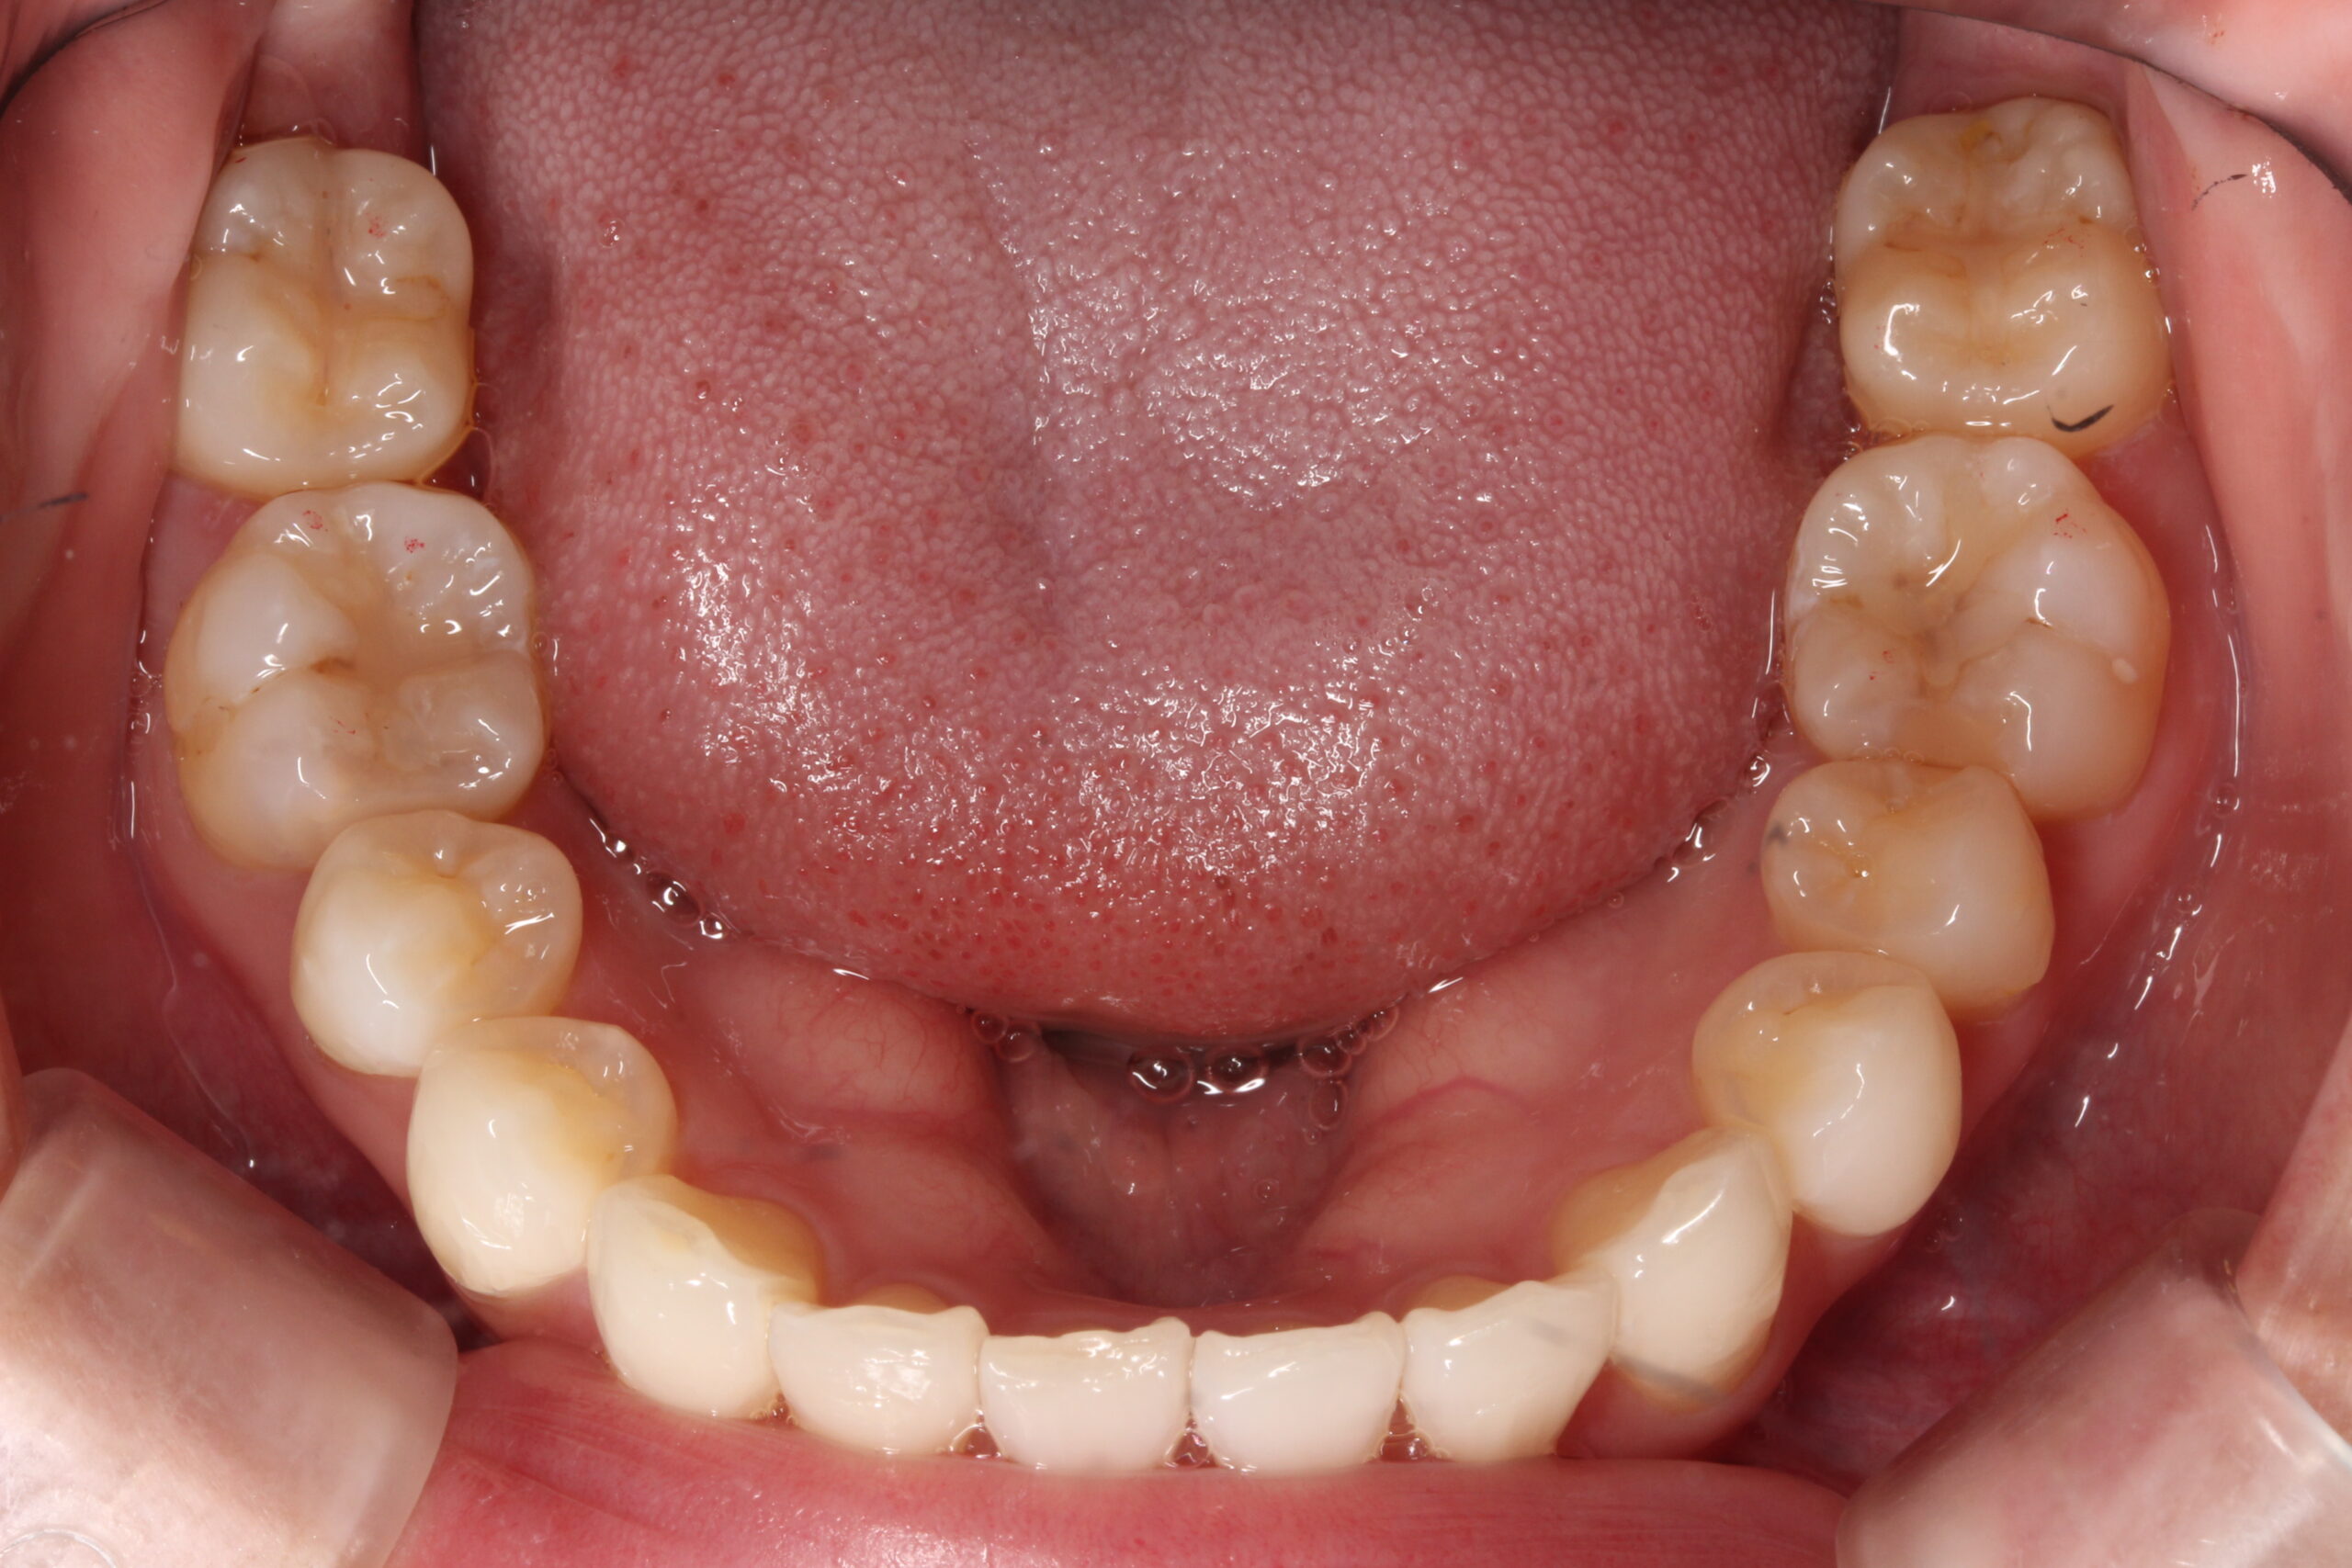

矯正術後:上顎

矯正術後:下顎